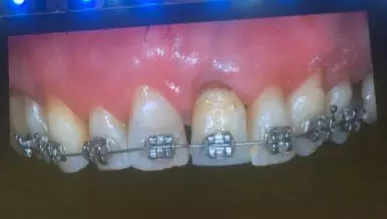

Prof. Carlo Maiorana展示了一例拔牙前聯(lián)合正畸治療獲得新骨形成的病例。該病例左上頜中切牙和側(cè)切牙需要拔除,x線顯示兩牙根距離較近、牙根頸部存在角形吸收,拔牙前通過正畸獲得新骨形成,然后拔牙即刻種植,終完成良好的牙冠修復(fù)。